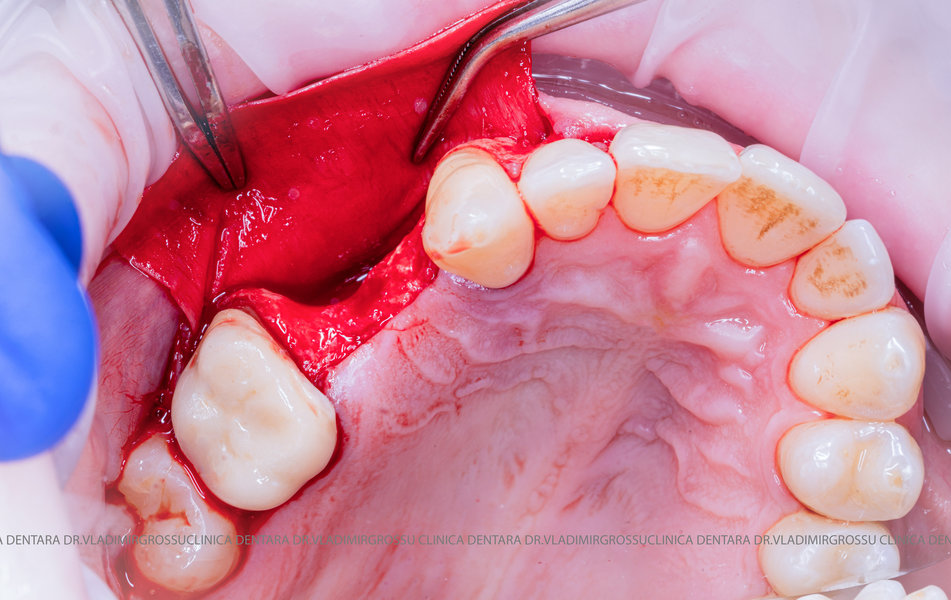

Stomatologia estetică reprezintă în prezent una dintre direcțiile principale de specializare a medicilor clinicii Dr. Grossu din Chișinău.Adiția sau augmentarea osoasă este o procedură chirurgicală prin care se refac defectele osoase rezultate în urma extracțiilor dentare, bolii parodontale sau traumelor dento-alveolare.

După extracția dentară, în intervalul de 6-12 luni, osul alveolar suferă un proces natural de remodelare, ceea ce conduce la scăderea volumului osos prin rezorbție. De aceea, inserția implantului dentar este ideală imediat după extracție sau, cel târziu, în primele 3-4 luni după aceasta.Scopul procedurilor de adiție osoasă este refacerea fundației osoase necesare pentru stabilizarea corectă a implantului dentar. Pentru ca un implant să reziste în timp la forțele masticatorii, este nevoie de o bază osoasă solidă și sănătoasă.

Aditia gingivală este o procedură chirurgicală ce corectează diverse probleme estetice și funcționale, cum ar fi recesiunea gingivală. În implantologia modernă, aditia de țesut moale este utilizată aproape în fiecare intervenție de inserție a implantului dentar pentru a asigura un aspect estetic natural și o bună integrare a implantului în cavitatea bucală.